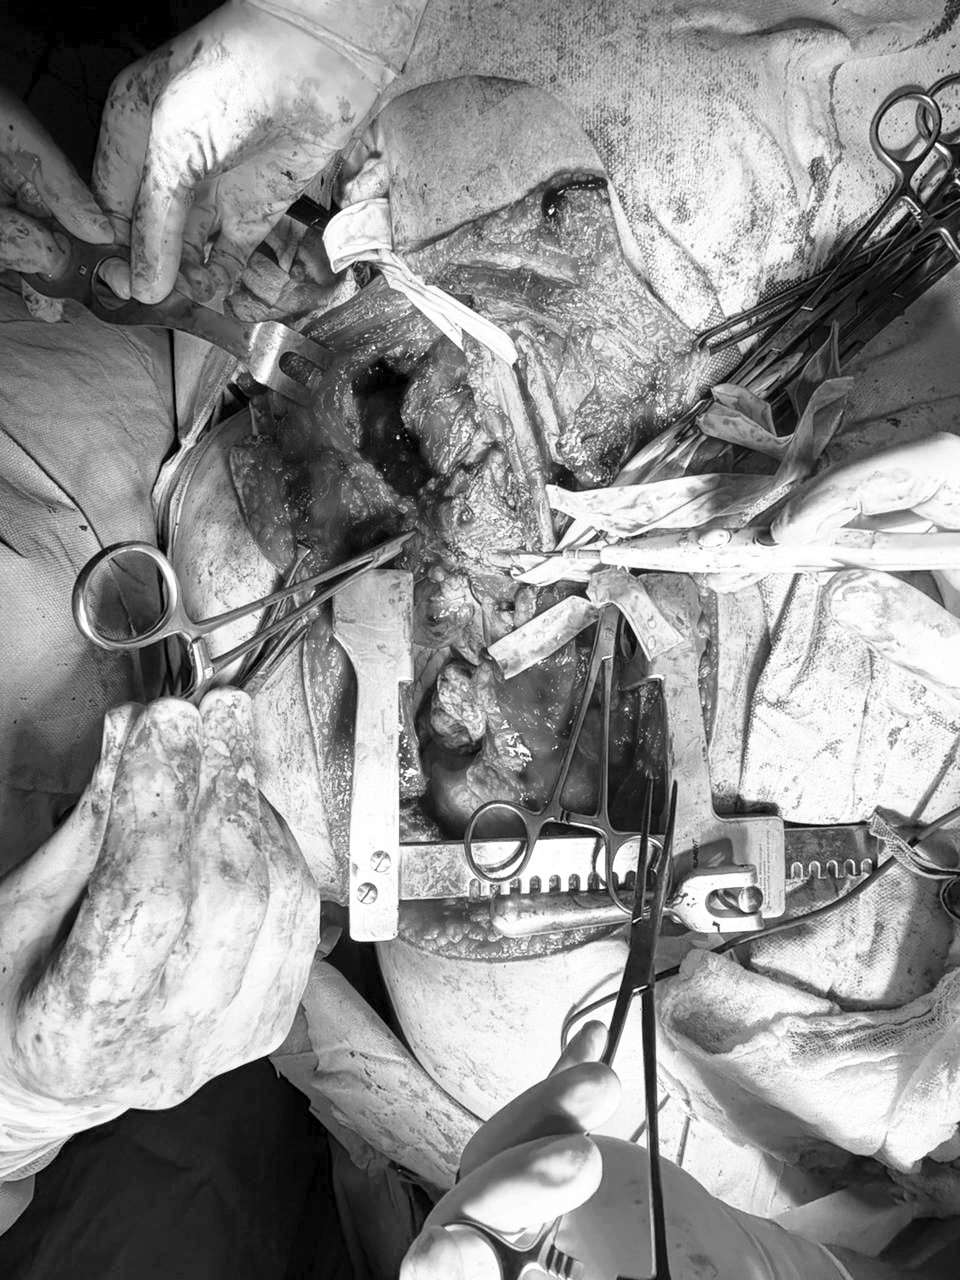

Durante la operación, los médicos encontraron un tumor de unos 20 centímetros de largo y 10 de diámetro. Era de forma irregular y bordes poco definidos. Estaba ubicado en la parte lateral del cuello, entre los músculos escalenos, pegado a la vena yugular interna con afectación de la vértebra cervical 7 y torácica 1 con invasión del canal medular. Además, llegaba hasta el tórax, cerca de la tráquea, y estaba firmemente adherido al plexo braquial derecho.

La cirugía combinó varias técnicas señala la profesional donde se hizo una incisión en el cuello y otra en el tórax con apertura parcial del esternón, conocida como hemiclamshell. También se colocó una placa y malla para fijar las vértebras cervicales y se descomprimió la médula espinal.